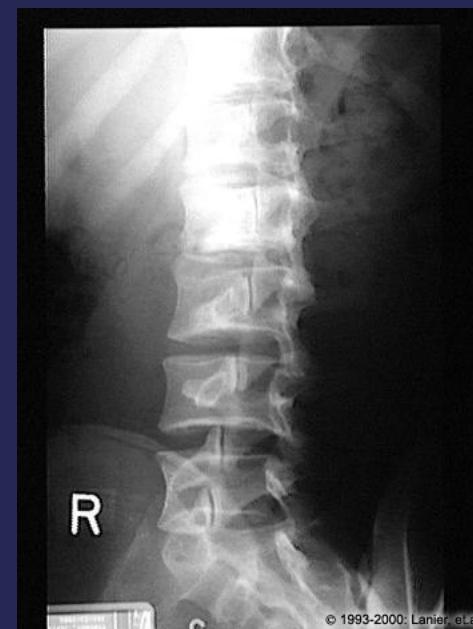

Imaging for Spinal Disorders

X-Ray

- AP, LAT, OBLIQUE views

- Flexion-Extension LAT

- Deformity series (e.g., scoliosis series)